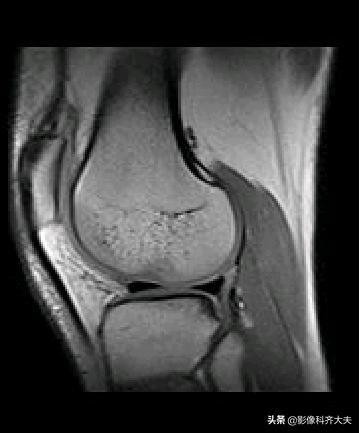

正常半月板MRI冠状位图像

正常半月板MRI矢状位图像